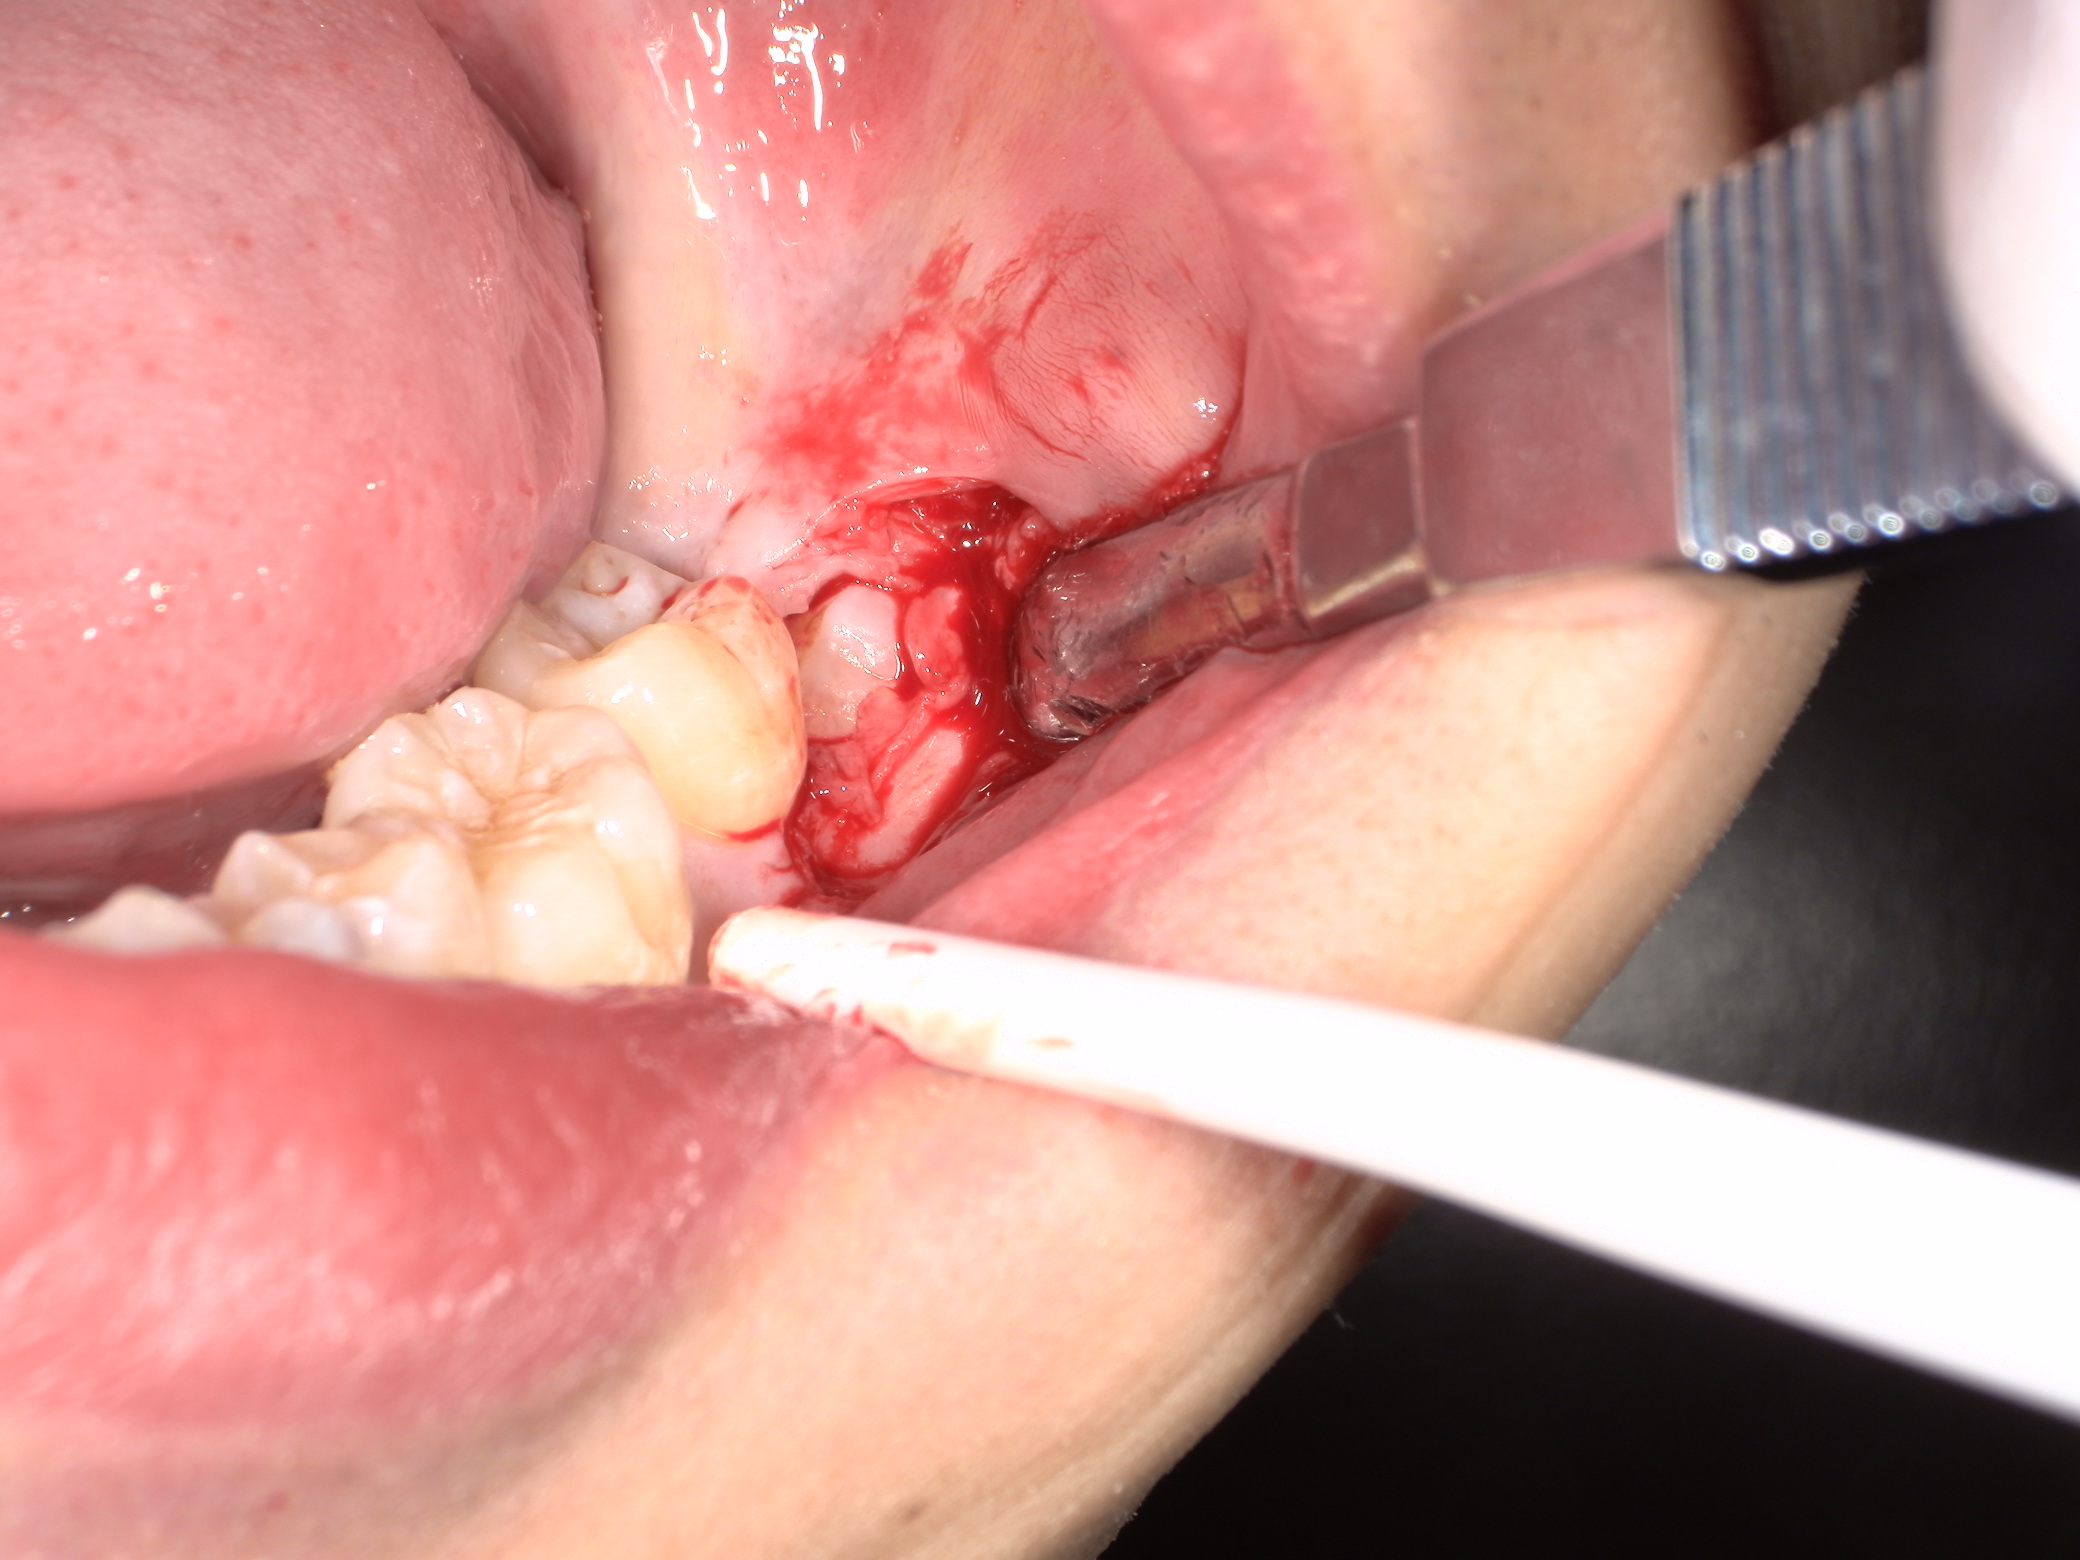

切開して歯冠部周囲の骨を削ります。

頭を囲む骨はなくなり、親知らずの歯冠部が見えてきましたがまだ抜けません。歯は基本的に頭側の方向にしか抜けません。

斜めに向いているのでこのままでは手前の歯にぶつかってしまいます。